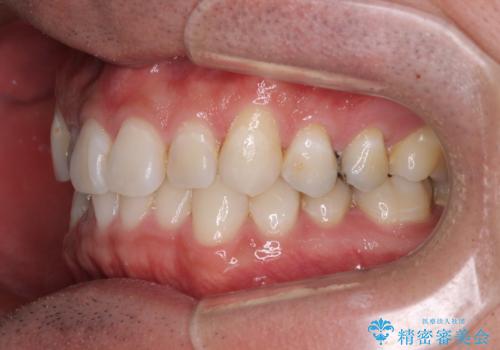

- 上下前歯の叢生を気にして来院された患者様です。

費用を抑え、期間もあまりかけずに治療をしたいとのことで、インビザライン・ライトを用いて矯正治療を行うこととしました。